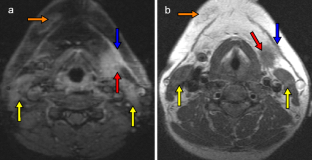

The aim of the study was to determine objective radiological signs of danger to life in survivors of manual strangulation and to establish a radiological scoring system for the differentiation between life-threatening and non-life-threatening strangulation by dividing the cross section of the neck into three zones (superficial, middle and deep zone). Forensic pathologists classified 56 survivors of strangulation into life-threatening and non-life-threatening cases by history and clinical examination alone, and two blinded radiologists evaluated the MRIs of the neck. In 15 cases, strangulation was life-threatening (27%), compared with 41 cases in which strangulation was non-life-threatening (73%). The best radiological signs on MRI to differentiate between the two groups were intramuscular haemorrhage/oedema, swelling of platysma and intracutaneous bleeding (all p = 0.02) followed by subcutaneous bleeding (p = 0.034) and haemorrhagic lymph nodes (p = 0.04), all indicating life-threatening strangulation. The radiological scoring system showed a sensitivity and specificity of ≈70% for life-threatening strangulation, when at least two neck zones were affected. MRI is not only helpful in assessing the severity of strangulation, but is also an excellent documentation tool that is even admissible in court.